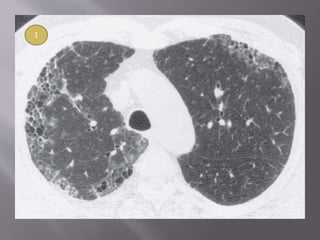

 A confident diagnosis of IPF on HRCT requires clinical

exclusion of known causes of UIP and the presence of all of

the following four criteria: reticular pattern, honeycombing,

subpleural and basal predominance, and absence of atypical

features.

 Typical HRCT findings- GGO , irregular linear

opacity ( reticulations ), traction bronchietasis.

 GGO found in patients , changed into reticular

opacity after few years.

 Honeycombing, if present, tends to be mild

 Lower lobe predominance is common. Upper

lobe is uncommon in NSIP and should suggest

another diagnosis (chronic HP, sarcoidosis)